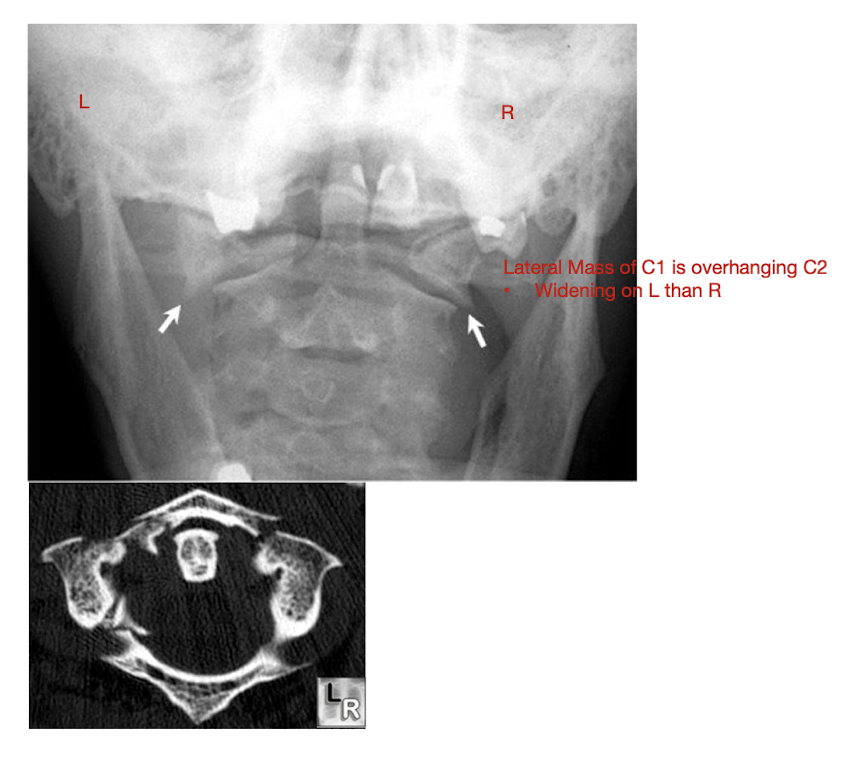

Fracture of C1: Jefferson Fx

Fracture of C1: Jefferson Fx

Rarely causes ___ injury

What direction of neck movement can cause head to slide forwards and compress SC?

Requires what type of view to diagnose?

Note displacement of what structure?

Neurological Injury

Fwd flex w Jefferson Fx

Open mouth view

Lateral Mass Displacement